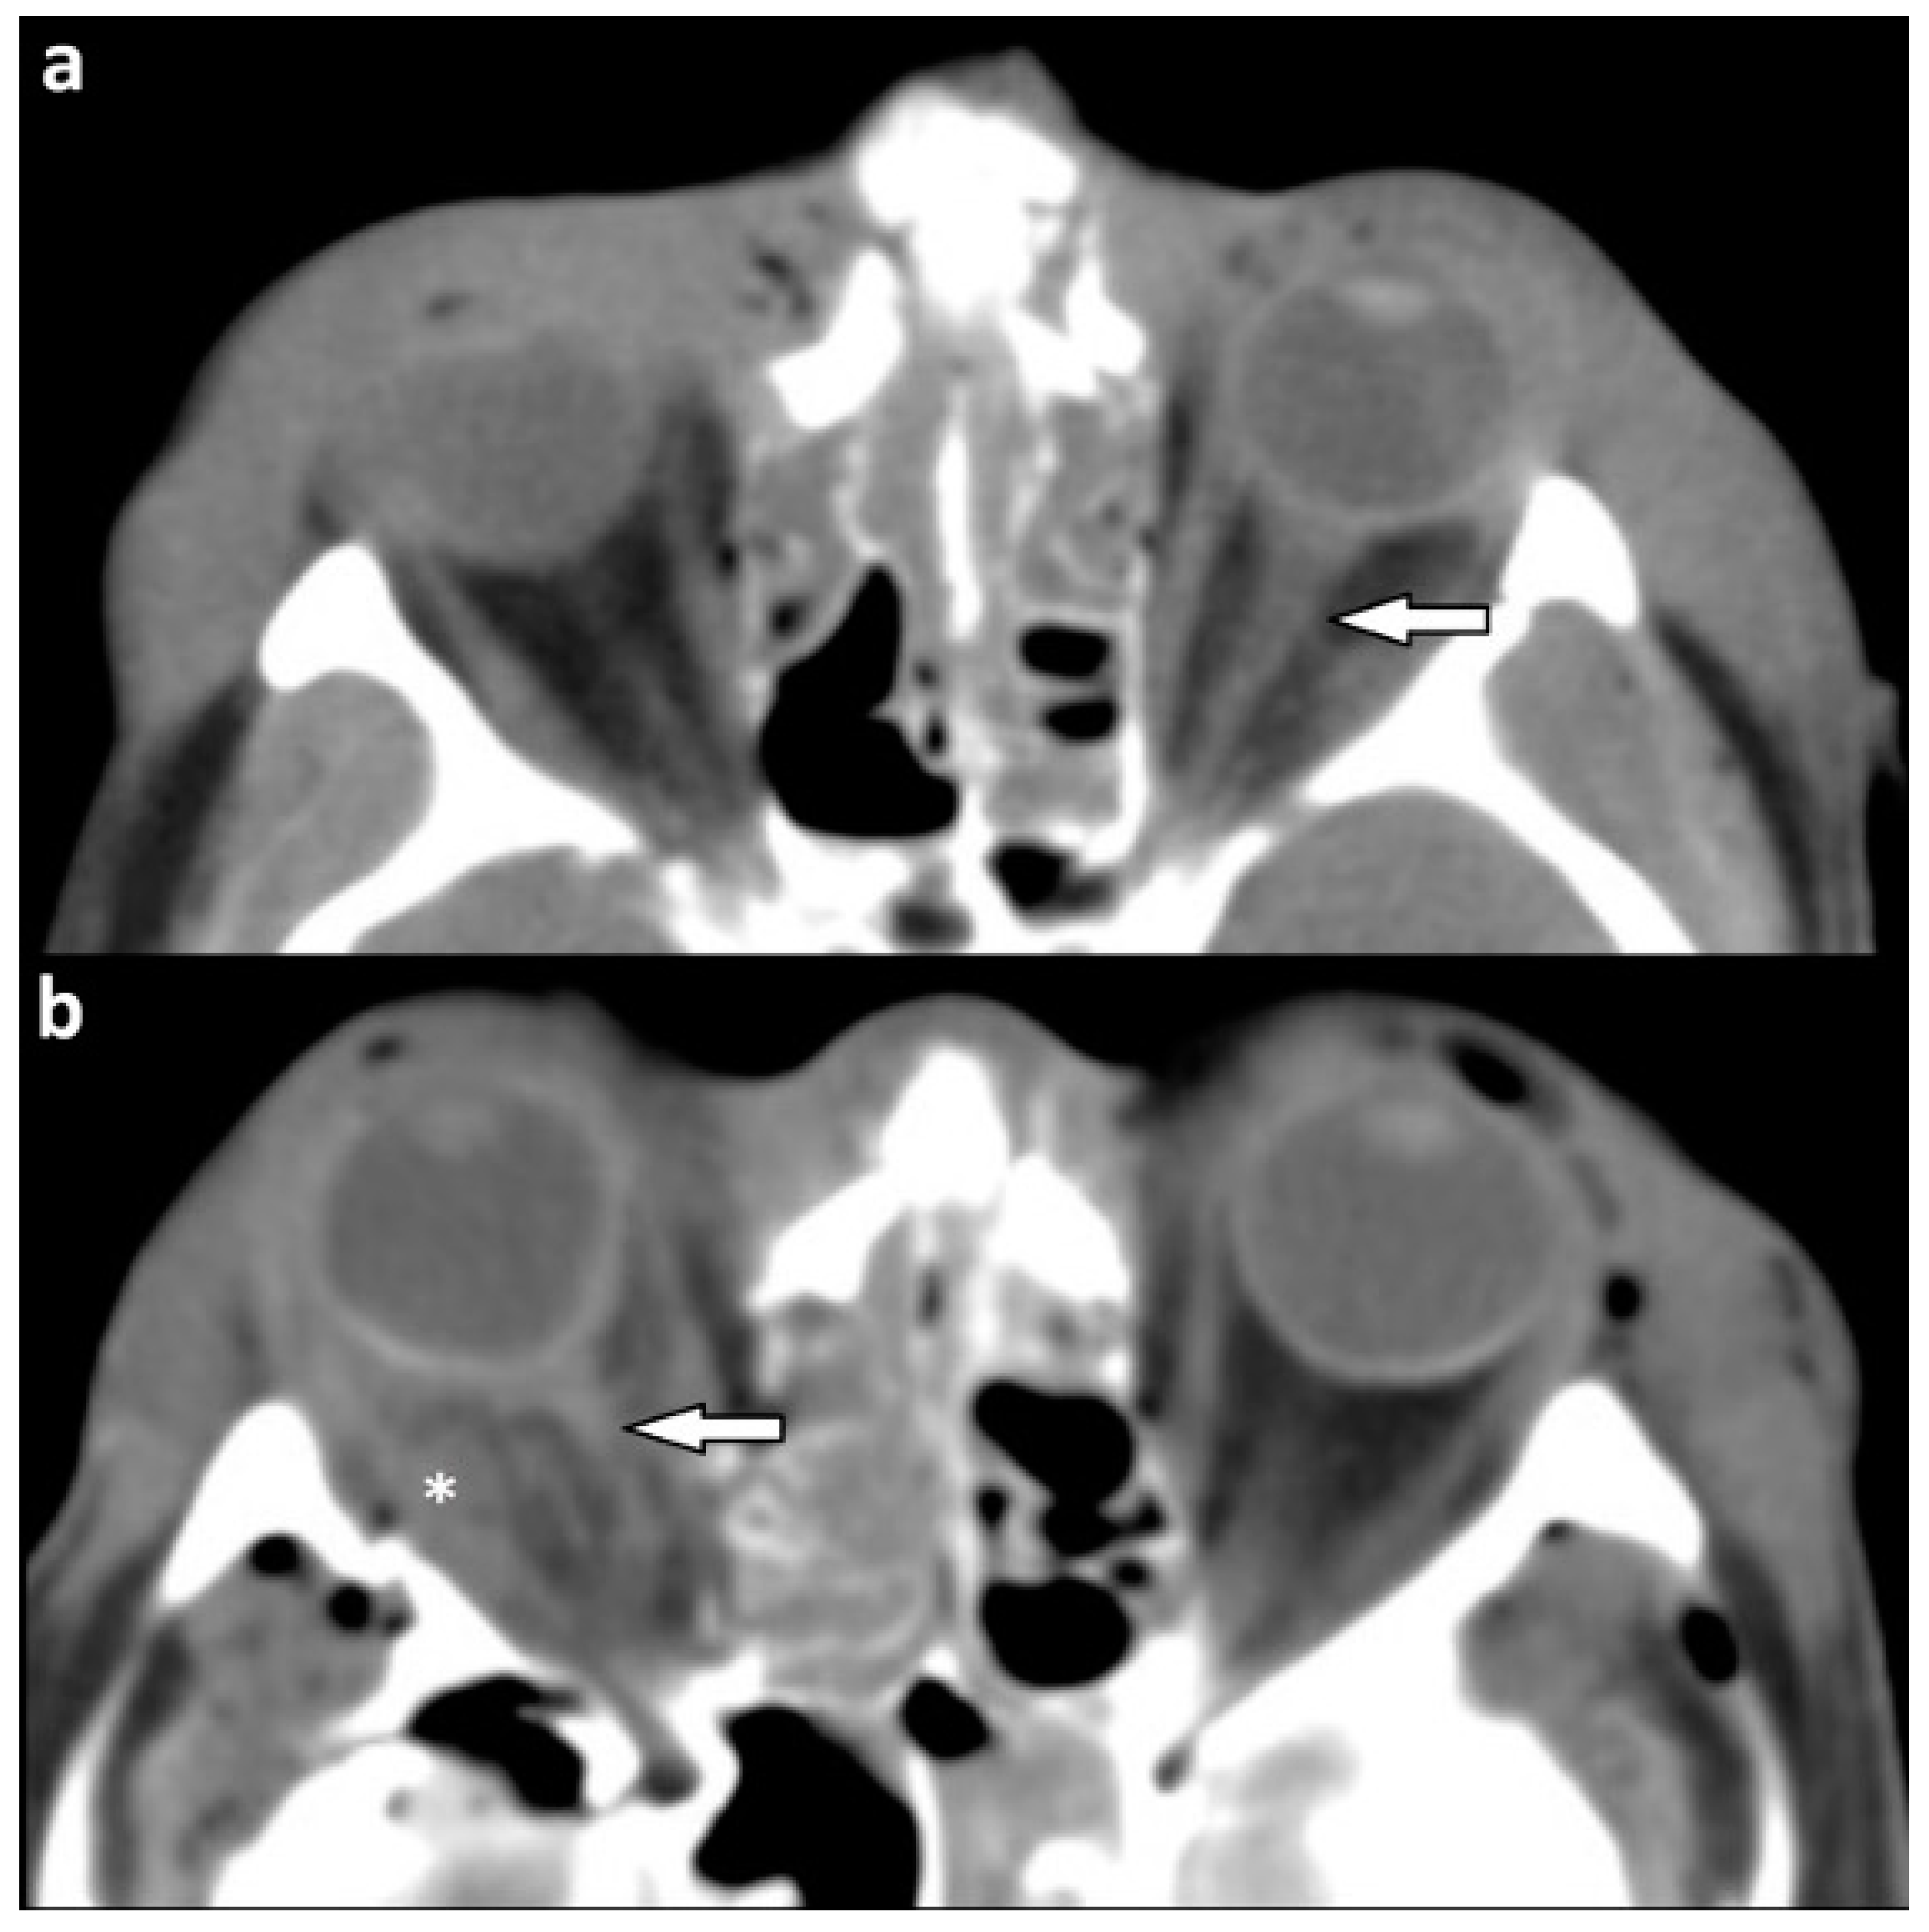

| Optic nerve | 24 (23.8) | |

| elongation | 13 (12.9) | |

| otherwise altered morphology | 10 (9.9) | |

| Orbital vessels | 16 (15.8) | |

| dilated superior ophthalmic vein | 10 (9.9) | |

| direct carotid cavernous fistula | 6 (5.9) |